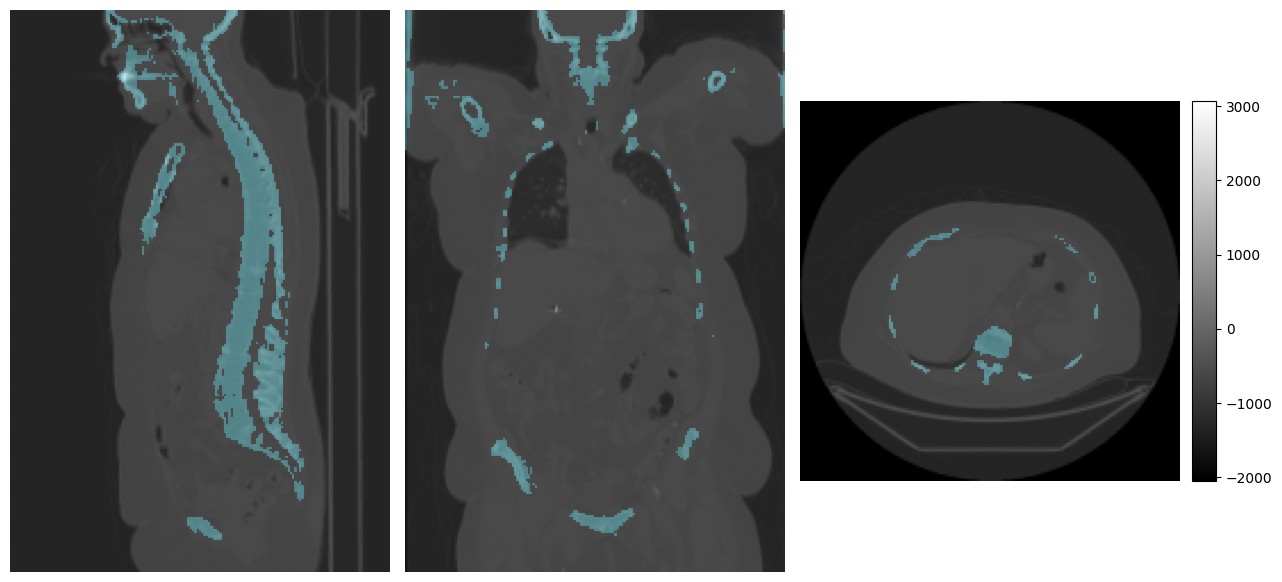

# Visualize the prediction

print("Prediction:")

mpr_plot(ct_image[0], labels=pred_segmentation[0])

Prediction:

../../_images/tutorials_imfusion-sdk_4_model_inference_7_3.png

[5]:

# Compute the dice score

dice_score = ml.DiceMetric().compute_dice(pred_segmentation, bones_segmentation)

# dice_score structure: List refers to each image in the image set, in this case only 1

# Dict refers to the label values, 0 = background, 1 = bone.

print(dice_score[0])

{1: 0.645042642699229}